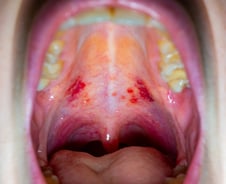

자궁경부암은 암 중에서 드물게 백신이 개발된 암이다. 예방할 수 있단 얘기다. 단, 자궁경부암 백신은 특정 HPV(인유두종바이러스) 유형의 감염 위험을 낮추는 예방 수단으로, 정기적인 선별검사를 병행해 조기에 발견하는 게 중요하다. 순천향대 부천병원 산부인과 김정철 교수는 "국가암등록통계에 따르면, 15~34세 여성의 자궁경부암 발생률은 2009~2013년 10만 명당 16. 7명이었다가 2014~2018년 14. 2명, 2022년 5명으로 줄어드는 추세이지만, 여전히 여성 건강을 위협하는 주요 암"이라고 말했다. 자궁경부암은 대부분 HPV 감염으로 발생하는 것으로 보고된다. HPV 백신 접종은 성적 매개를 통한 HPV 확산 감소뿐 아니라 여성의 자궁경부암 외 사마귀, 항문암, 구강암 등 HPV 관련 질환의 예방에도 효과적이다. 이에 최근 세계적으로 남성의 백신 접종도 권고하는 추세다. 자궁경부암 선별검사는 자궁경부 세포 검사를 통해 정상·비정상 세포 여부를 확인하는 검사다. 세포 검사에서 이상 소견이 확인되면, 조직검사 등 추가 검사를 통해 세포의 정확한 형상과 모양, 조직 내 위치 등을 병리학적으로 확인해야 한다.